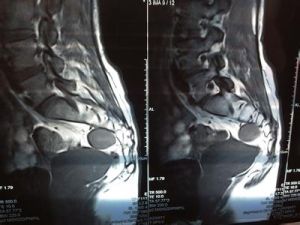

B超、CT與 MRI對盆腔腫瘤發生部位、良惡性以及腫瘤累及範圍大多能作出正確判斷 ,對大部分腫瘤能提示腫瘤的組織學類型 ,為臨床選擇合理的治療方案提供依據。